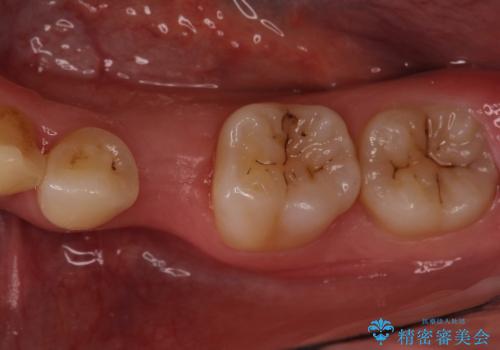

小臼歯のインプラント

- 小臼歯が先天性欠損していたため、インプラントにて補綴しています。

当院ではストローマンインプラントを導入しています。